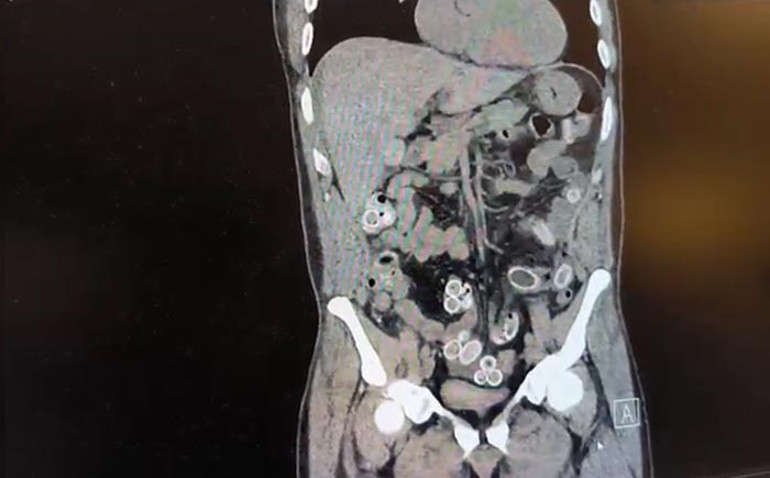

Fas’tan yaklaşık 3 bin kilometre uzaktan uçakla Türkiye’ye gelen Cüneyt G., 2 gün sonra karın ağrısı şikayetiyle Fulya’daki özel bir hastaneye başvurdu. Yapılan muayenenin akabinde Cüneyt G.’nin tomografisi çekildi. Mide ve bağırsaklarında yabancı madde tespit edilmesi sonrasında hastane yetkilileri durumu polis ekiplerine bildirdi.

ESRAR KAPSÜLLERİ AMELİYATLA ÇIKARILDI

İhbar üzerine harekete geçen Beşiktaş Asayiş Büro Amirliği ekipleri, doktorlarla görüşmeler gerçekleştirdi. Doktorların tespitleri neticesinde Cüneyt G.’nin bağırsaklarından toplam ağırlığı 259,7 gram olan 49 esrar macunu çıkarıldı. Ayrıca, şüpheliye ait bir cep telefonu da hastane yetkililerince polis ekiplerine teslim edildi.